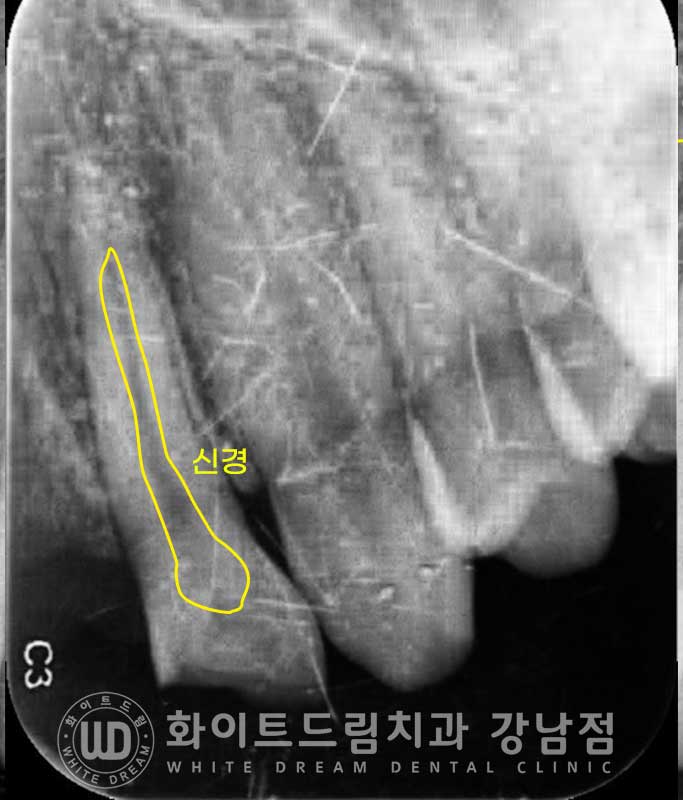

옆 부러진 22번 치아는 어떻게 치료를 할까요?

치아의 버리가 1/3 정도 부러져 있지만 잇몸뼈 위쪽으로

4-5mm 정도 치아가 넉넉하게 남아있습니다.

▲ 환자분의 22번 부러진 치아 치근단 사진입니다.

이런 치아들은 신경 감염의 위험성이 있기에 신경치료 후 크라운치료를 통해

치아의 기능을 다시 살려줄 수 있습니다.